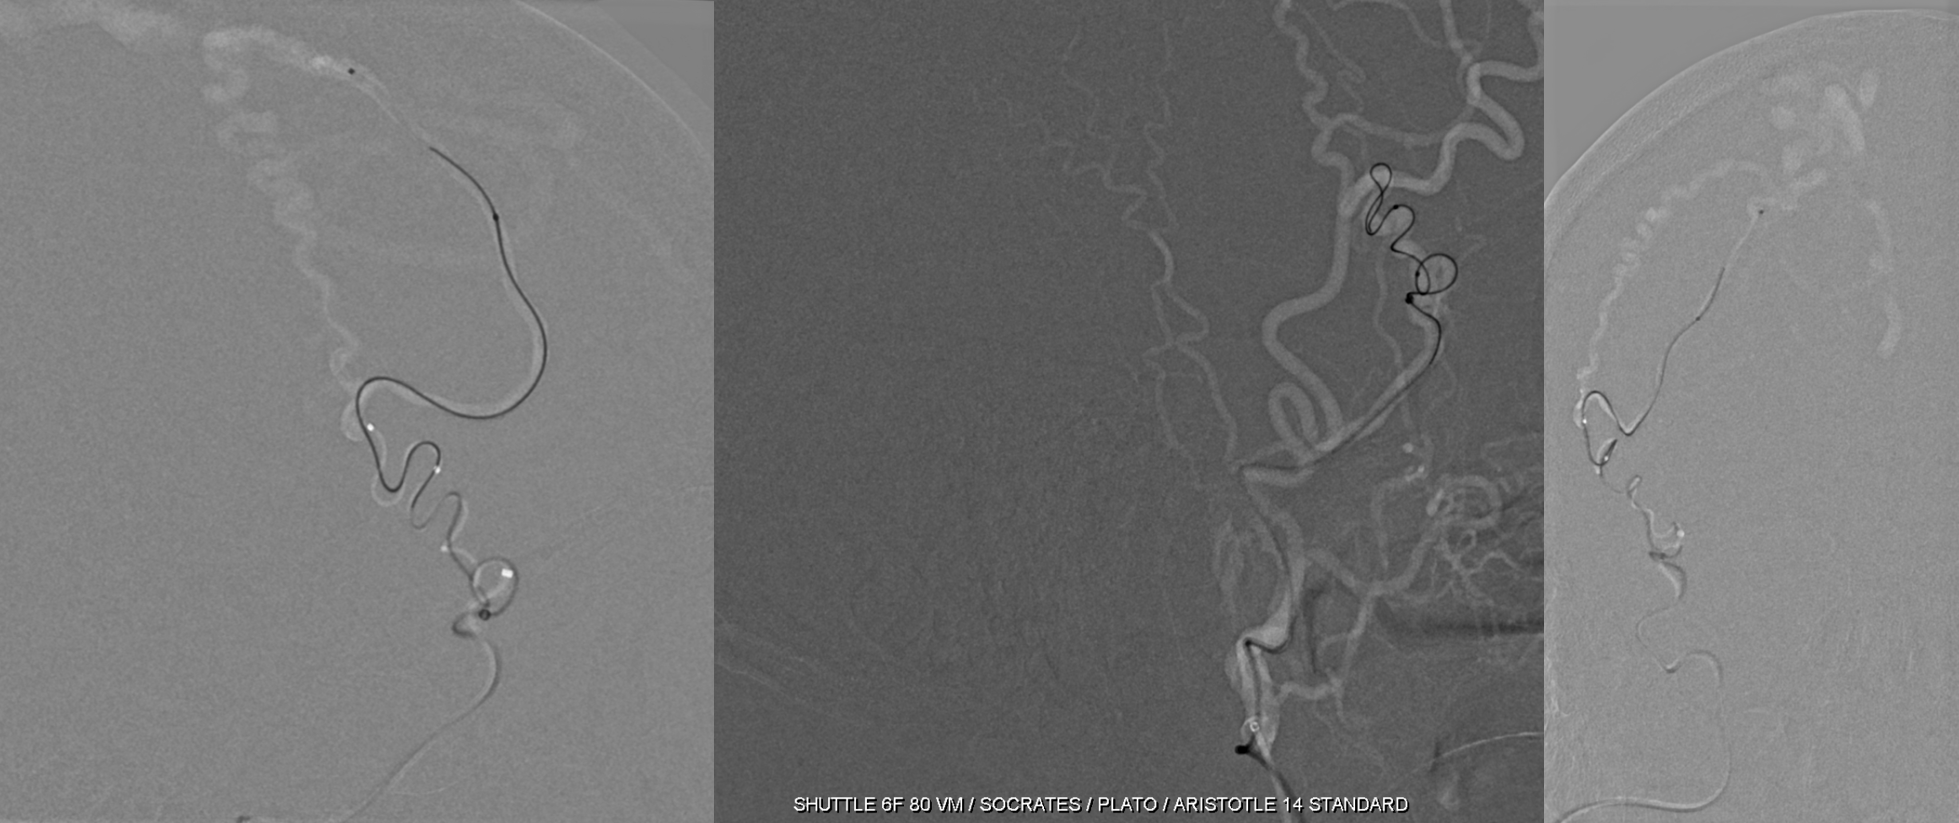

Access is challenging but not impossible with the right tools

Micro angio and onyx 18 cast. A mistake is made here